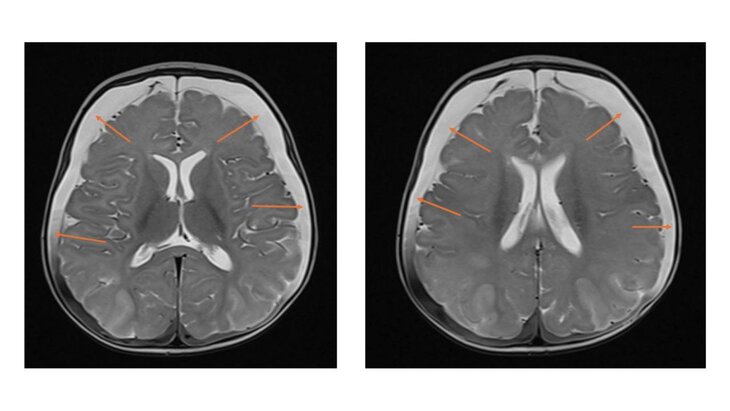

Результаты МРТ показали следы перенесенных кровоизлияний и серьезное нарушение кровоснабжения мозга. Был поставлен диагноз – ННН-синдром, при котором организм не способен перерабатывать белок, что приводит к отравлению мозга аммиаком.